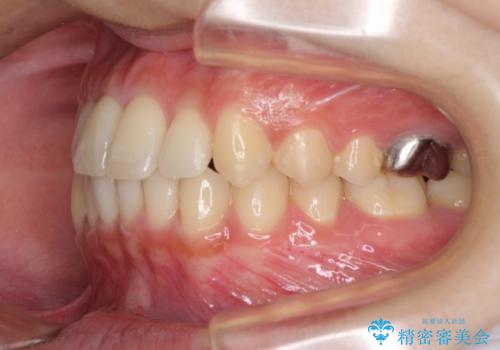

海外勤務中のインビザラインによる矯正治療

- 前歯のクロスバイトを気にして来院され患者様です。

定期的に日本には帰国するものの、日ごろは海外でお仕事をされているとのことで、インビザラインによる治療を希望されました。

トラブルが起こった時に対応ができない、来院を帰国のタイミングに合わせなければならないため治療が長期化するなど困難はありますが、ワイヤー矯正と比べると治療を進めやすいといったメリットがあるので、インビザラインにて矯正治療を行うこととしました。

治療期間が世界的な感染症の流行時期と重なったため、海外と日本での往来が困難となり、治療継続が懸念されました。

それでも、しっかりとマウスピースを装着してくださったので、大きなトラブルもなく治療を終えることができました。